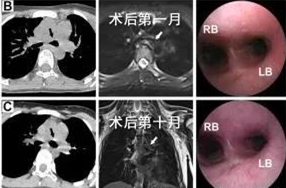

图3.术后随访中患儿胸部CT及气管镜检查

确定治疗方案后,胸外科医疗团队立即联系我院3D打印研究中心曹铁生教授和西安交通大学贺健康教授,首先利用我院自主研发的3D打印机为患儿制作了1:1气管模型,充分评估病情特点,然后为患儿量身定做了可降解的聚己内酯(PCL)外支架。2018年1月初,黄立军副主任为患儿施行了手术,术中在软化的气管外放置了PCL支架,挡开了来自左肺动脉干和胸主动脉的挤压,手术仅耗时1小时15分。术后连续对患儿随访视察10个月,患儿塌陷的左主支气管已完全复张,PCL支架也逐渐降解吸收,患儿术后1月开始上学,回归了正常的生活。